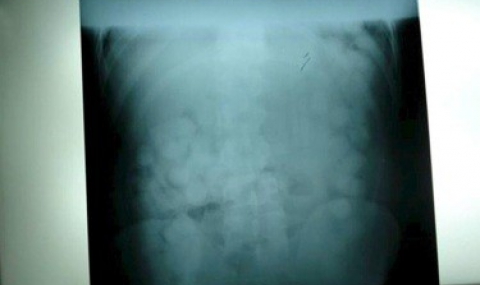

Групата опитала да осъществи трафик на кокаин във вид на 90 капсули с общо тегло 1,1 кг, погълнати от Мартин К. Установено е, че наркотичното вещество е било предназначено за разпространение на територията на страната ни.

От шестимата само у Мартин са намерени капсули в корема. Той е настанен под охрана от служители на БОП в хирургично отделение на петричката болница. Етажът на отделението се охранява.

След като са му дадени слабителни и му е направена клизма, гълтачът изхвърлил около половината от капсулите. Тъй като има технологично време, за което капсулите се разтварят, се наложила оперативна интервенция, за да се изкара цялото количество наркотик.